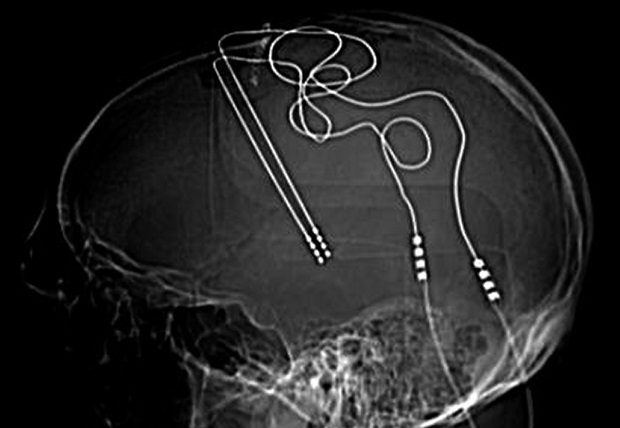

Na prática, o tratamento consiste em uma bateria com condutores especiais implantados na cabeça do paciente, programados para estimular periodicamente de forma controlada determinadas regiões do cérebro. O DBS já foi aprovado nos Estados Unidos para tratar epilepsia, transtorno obsessivo-compulsivo e transtornos do movimento, como a doença de Parkinson, e se espera que a técnica também possa mudar os padrões de atividade anormal nos circuitos neurais que causam os sintomas de depressão.

Recentemente, entretanto, estudos com objetivo de testar a estimulação do SCC como um tratamento para depressão renderam resultados muito abaixo do esperado. A hipótese é que diferenças sutis em onde os cirurgiões colocam os eletrodos são responsáveis pela variação nos resultados dos pacientes. Portanto, o grupo de Helen Mayberg busca uma abordagem de ressonância magnética chamada tractografia para visualizar localizações de feixes de nervos e eletrodos-alvo com mais precisão.